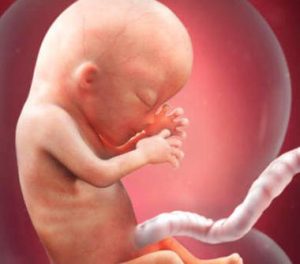

Een nieuw trimester begint en dus ook een nieuwe fase voor het kleintje in je baarmoeder. Tijdens week 13 van je zwangerschap is je baby reeds 6,5 tot 10 cm lang en hij weegt tussen de 13 en 20 gram.

Het gezicht van je baby vormt zijn unieke gelaatstrekken, maar ook andere transformaties vinden plaats die we hieronder zullen bekijken. Het is ongelooflijk spannend allemaal!

De uiteindelijke locatie van je baby’s ogen en oren is al bepaald. Daarnaast is er nog een ander werkelijk fascinerend detail: de vingerafdrukken zijn reeds gevormd.

De hersenen zijn één van de meest ontwikkelde delen van de foetus. Net zoals de structuren die de organen omhullen en beschermen.

Vanaf week 13 van je zwangerschap vormt het hoofd de helft van de totale grootte van de foetus.

Vanaf nu zal het lichaam sneller groeien om die achterstand in te halen en zodoende een proportioneel lichaam vormen.

In feite is tijdens de geboorte het hoofd slechts een vierde van de totale grootte van het lichaam. Bovendien zijn er enkele interessante processen in verband met het lichaam van de foetus en zijn functie.